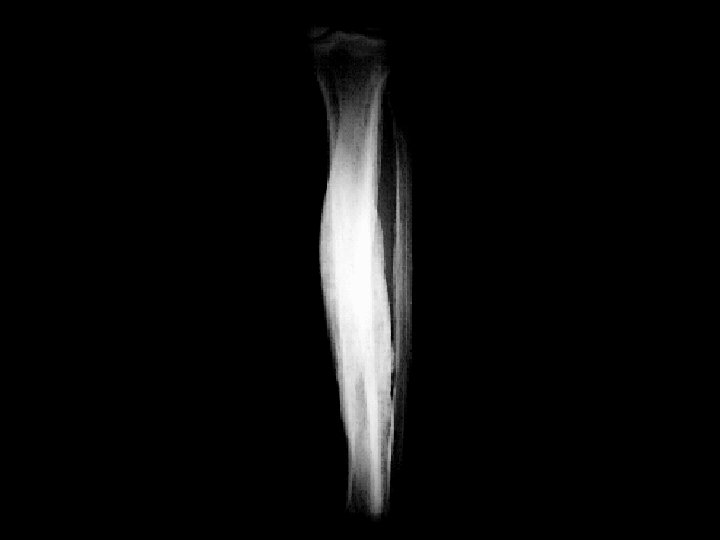

Engelmann’s disease • Findings: – Increased diaphyseal activity and expansion of the lower extremities – Radiographs show marked of the diaphyseal corticies affecting both periosteal and endosteal surfaces – Progressive diaphyseal dysplasia; autosomal dominant, variable expression • ddx: – Osteopetrosis – Melorhostosis – Hyperphosphatasia – Fibrous dysplasia